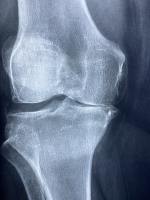

관절은 뼈와 뼈 사이를 부드럽게 연결하는 역할을 하며, 연골과 활액(윤활액)이 마모되면 통증과 염증이 발생하게 됩니다. 퇴행성 관절염, 류마티스, 스포츠 손상 등으로 인해 관절 보호가 필요할 때, 영양제를 통한 보조 치료는 증상 완화에 도움이 됩니다.

콘드로이친

기능: 연골에 수분을 공급하고, 연골의 탄성과 구조를 유지시켜주는 기능을 합니다.

- 관절 마찰 감소로 통증 경감

- 연골세포 퇴화를 억제하고 회복 도움

- 연골 연화증 예방 및 장기적인 관절 보호